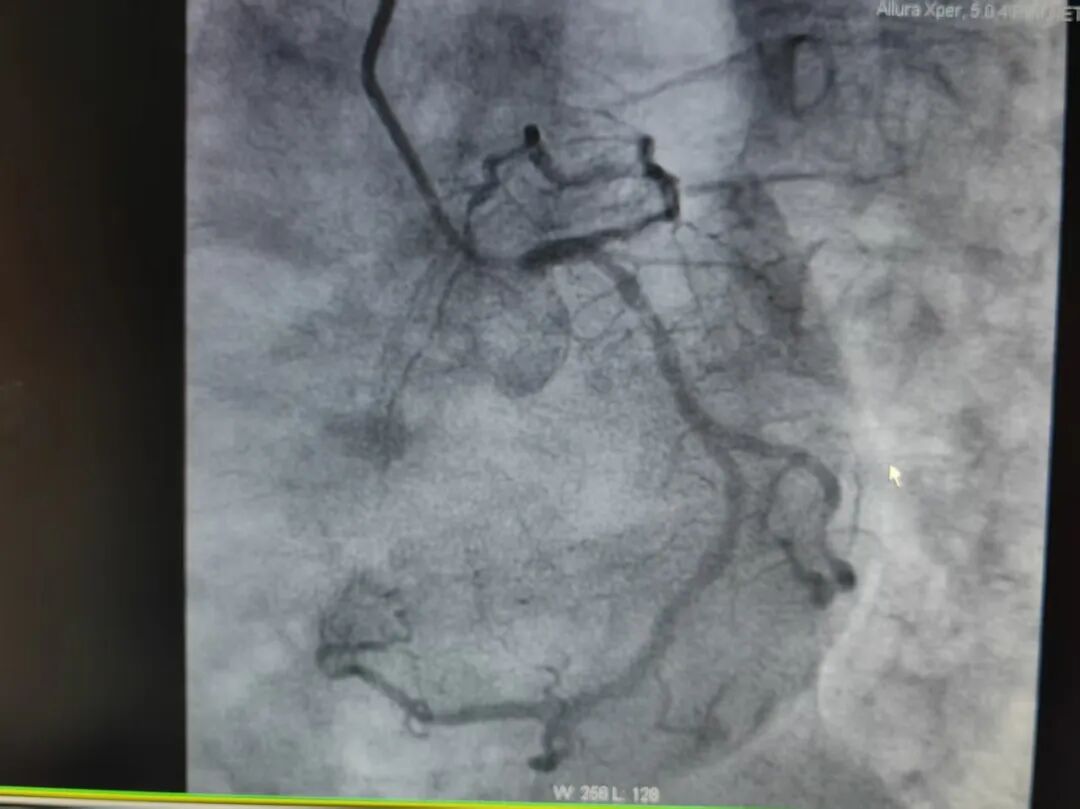

手术中,葛海龙教授全程指导,冯源海主任团队精准操作,经过精准旋磨后,前降支管腔狭窄程度得到显著改善,血流通畅性恢复,随后团队顺利完成球囊扩张及支架植入术。整个手术过程顺利,患者生命体征平稳,术后恢复良好,胸痛症状已明显缓解。

冠状动脉旋磨术是治疗严重冠脉钙化病变的 “利器”,尤其适用于常规介入手段难以处理的复杂钙化病变。该技术通过物理研磨的方式消除钙化斑块,为后续支架植入创造良好条件,能有效提高手术成功率,降低并发症风险。此次兴安盟人民医院首例冠脉旋磨术的成功实践,不仅验证了我院心内一科介入团队的技术实力和应急处置能力,更借助与北京安贞医院的学术合作与技术支持,让区域内患者无需远赴异地,就能享受到国内顶尖水平的介入诊疗服务。